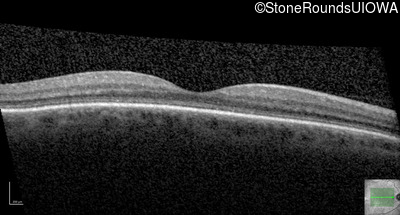

OCT Stack

20/400 sc

OD

OS

20/200 sc

10/160 -1 sc